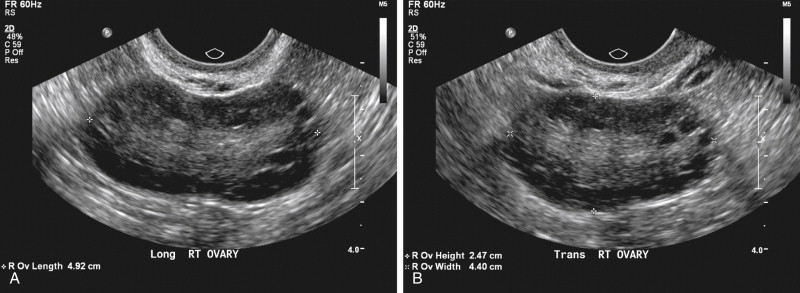

ظاهر پلیکیستیک تخمدانها در سونوگرافی

سونوگرافی تخمدانها